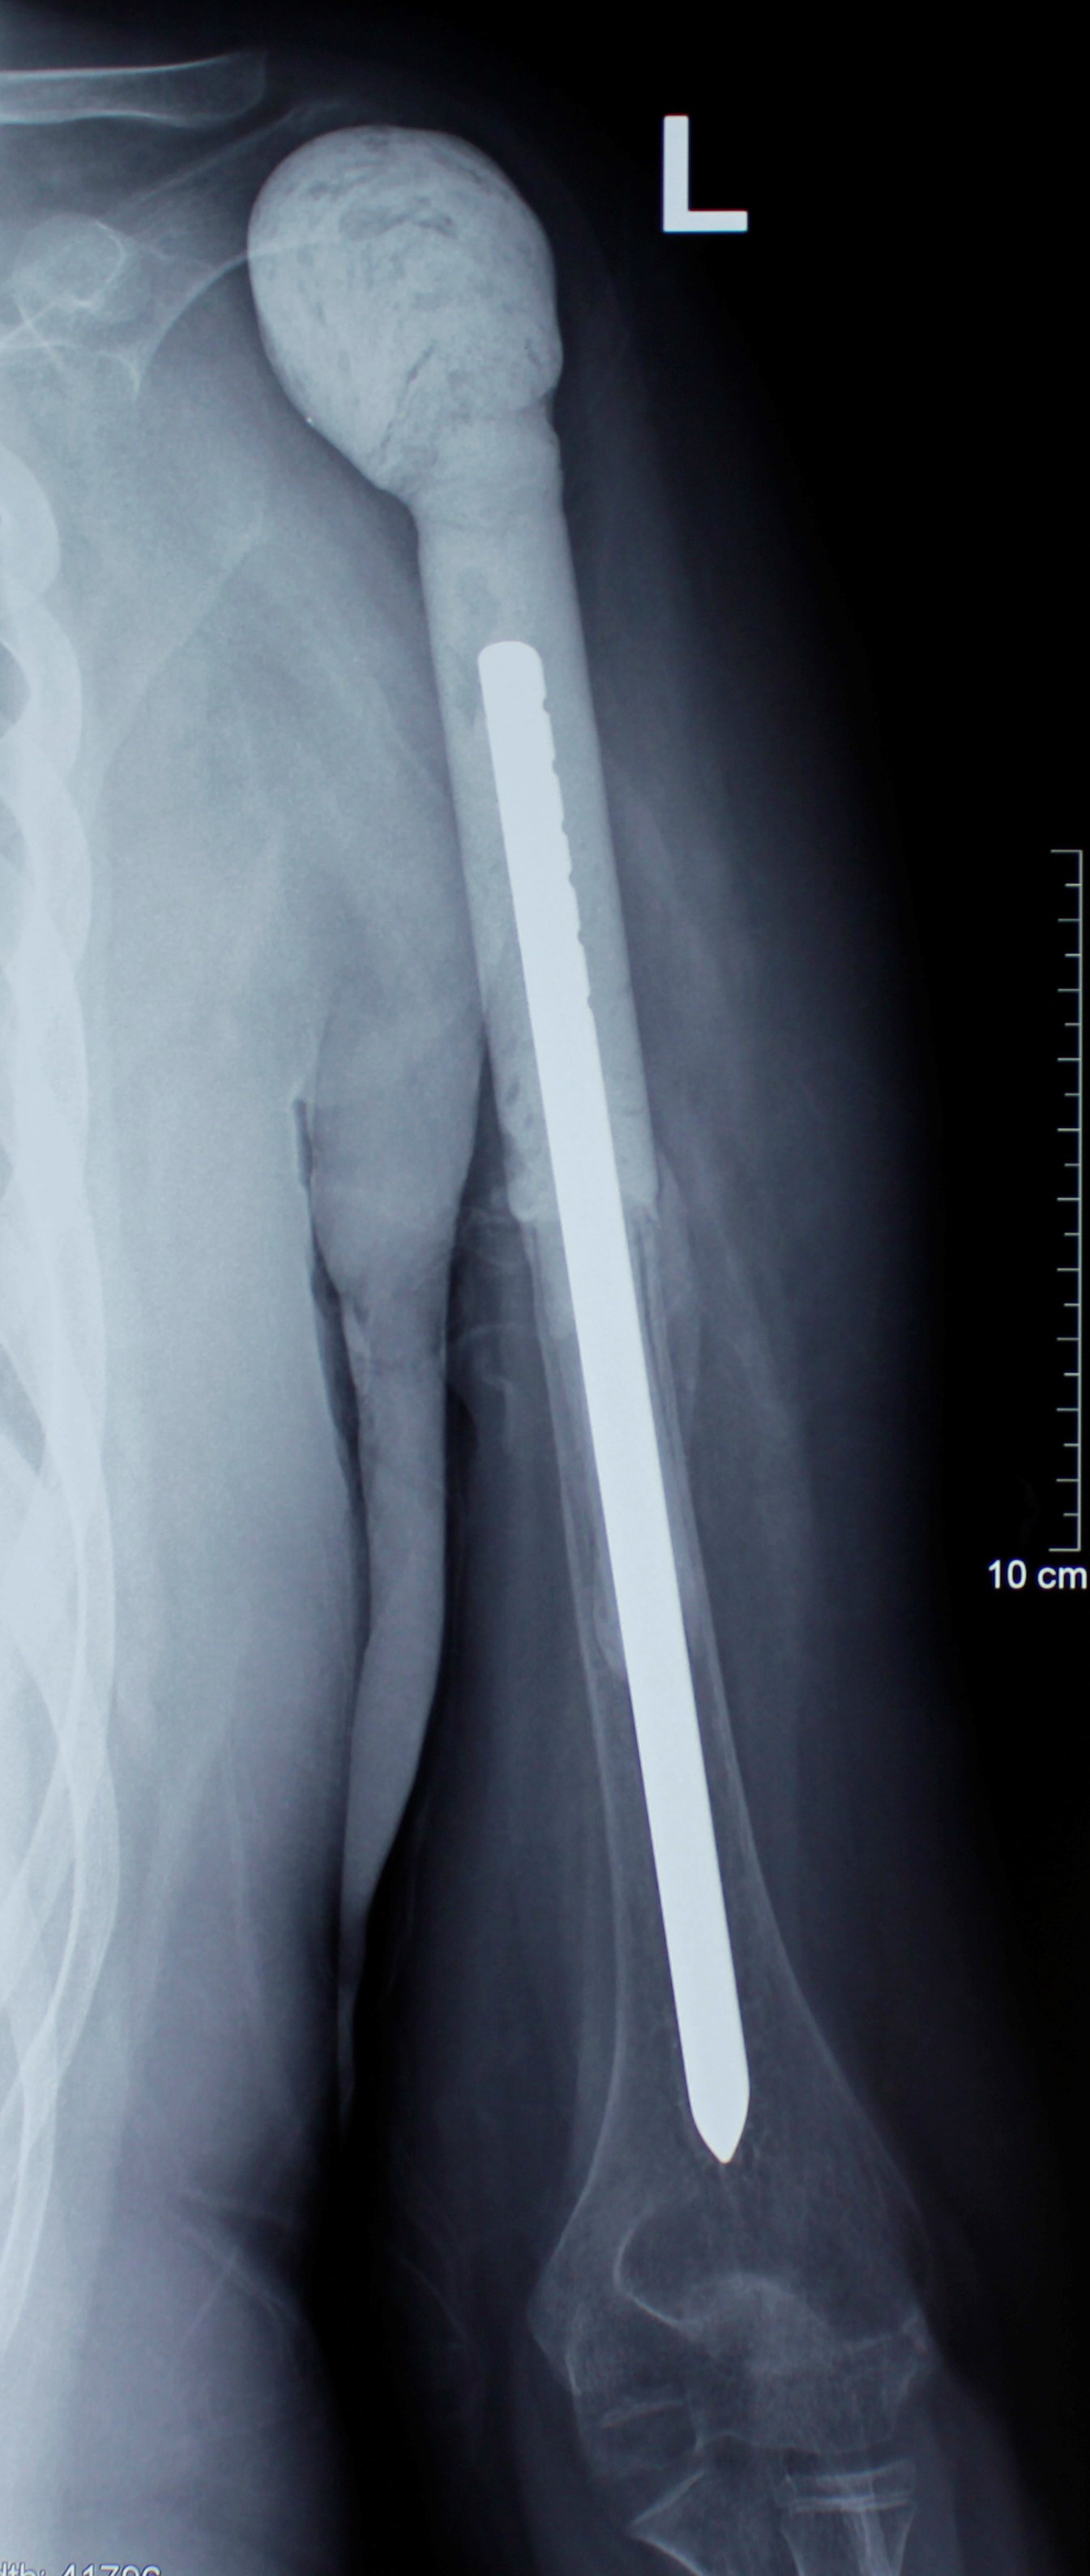

4. Гигантоклеточная опухоль верхней трети плечевой кости

У 14-летнего ребенка был литический вариант гигантоклеточной опухоли с выраженным мягкотканным компонентом, врастающим в подмышечную клетчатку и дельтовидную мышцу. Произведено удаление опухоли путем резекции верхней части плечевой кости, образовавшийся дефект был восстановлен металло-цементным спейсером. Этот метод позволяет оперировать больных с костными опухолями в максимально краткие сроки, во избежание прогрессирования заболевания.

После операции